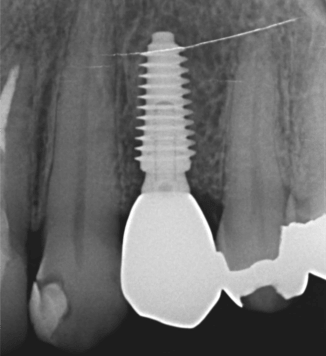

症例4【50代女性】左上6 副鼻腔膜を挙上しインプラント埋入 左上5 歯根破折の為インプラント埋入

治療前

左上5の歯根破折

治療後(10年経過)

※説明

主訴 左上奥歯で物が噛めない。入れ歯は煩わしいので、インプラントを希望。

左上第一大臼歯欠損部位は、骨の高さが3~4㎜しかなく、造骨の為にソケットリフト(骨造成)を行い、骨の高さを確保しインプラントを埋入。

約半年の免荷期間を経て、仮歯を装着、リハビリをし、約7ヶ月後にメタルボンド(金属焼付ポーセレン)を装着。

その後、左上第二小臼歯の歯根破折の為に、2本目のインプラントを埋入。(抜歯即時埋入)

リスクとしては、外科的侵襲がある。デメリットは、保険外診療の為、経済的負担がある。

費用 111万(オペ。ソケットリフト・人工骨・採血による濃縮血小板生成・仮歯・最終補綴物まで含む)